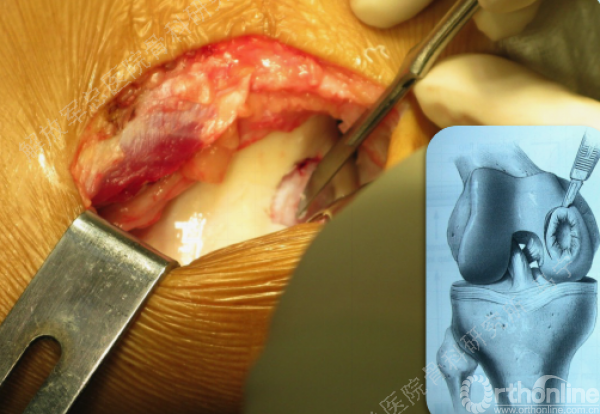

切开后可以看见很明显的软骨破坏。

对糜烂的软骨进行清创,按照损伤的面积裁剪软骨补片进行修补。